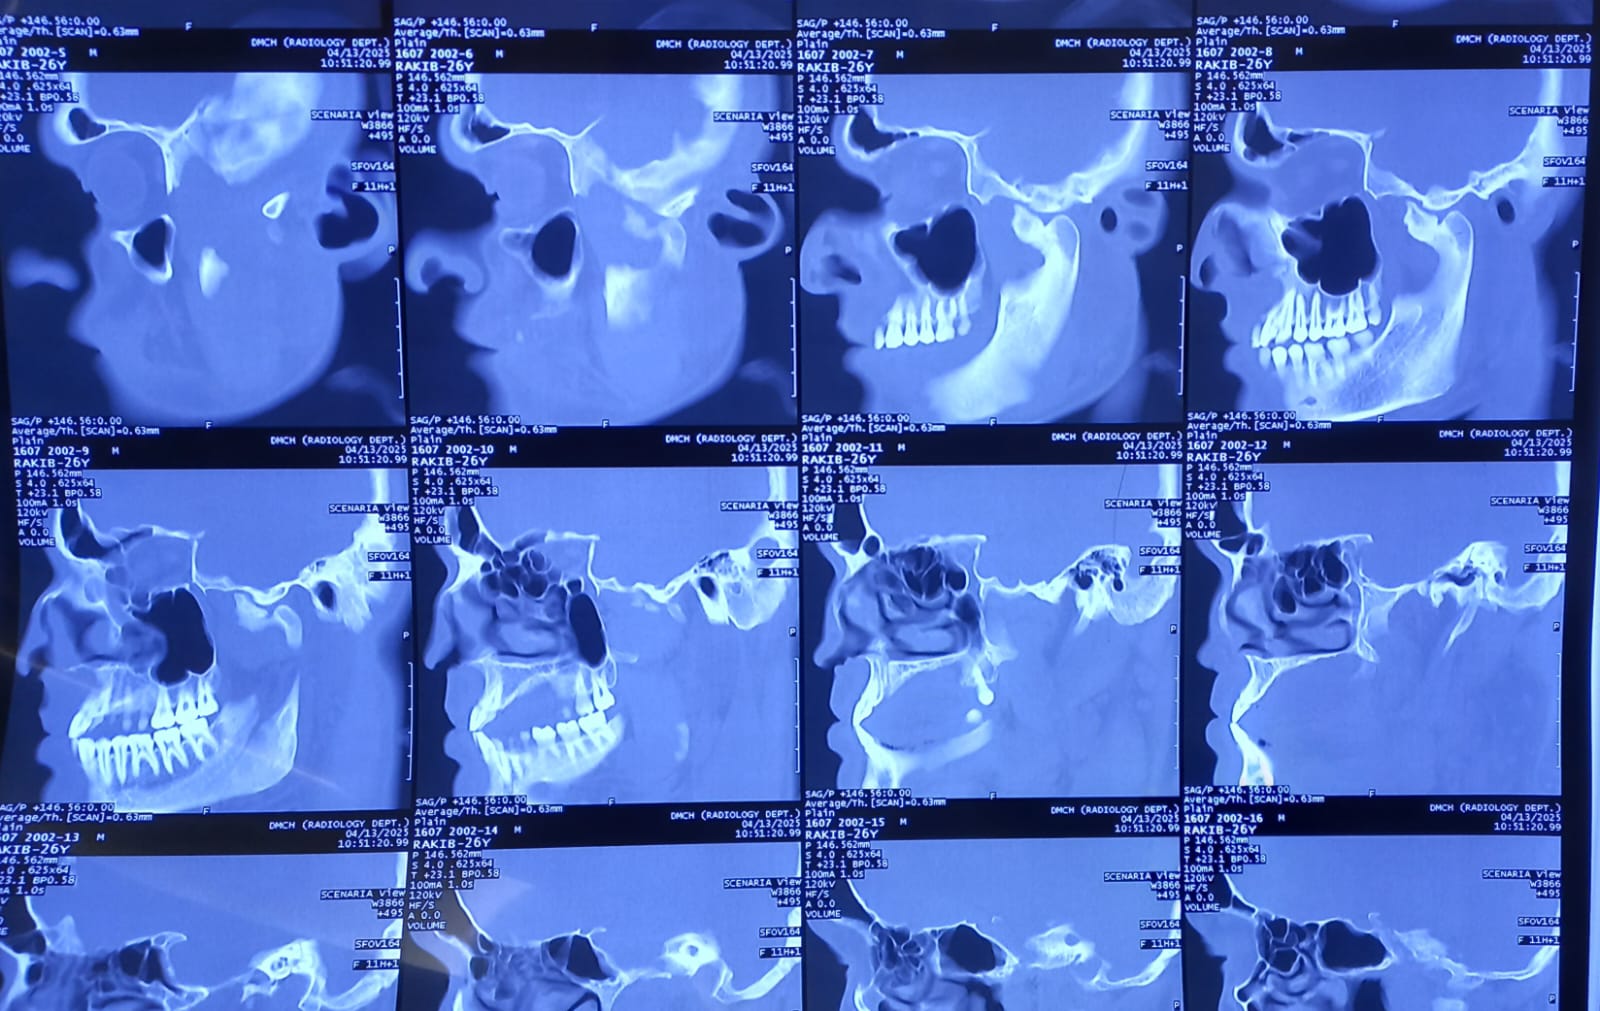

Rafis Dental and Maxillofacial Center